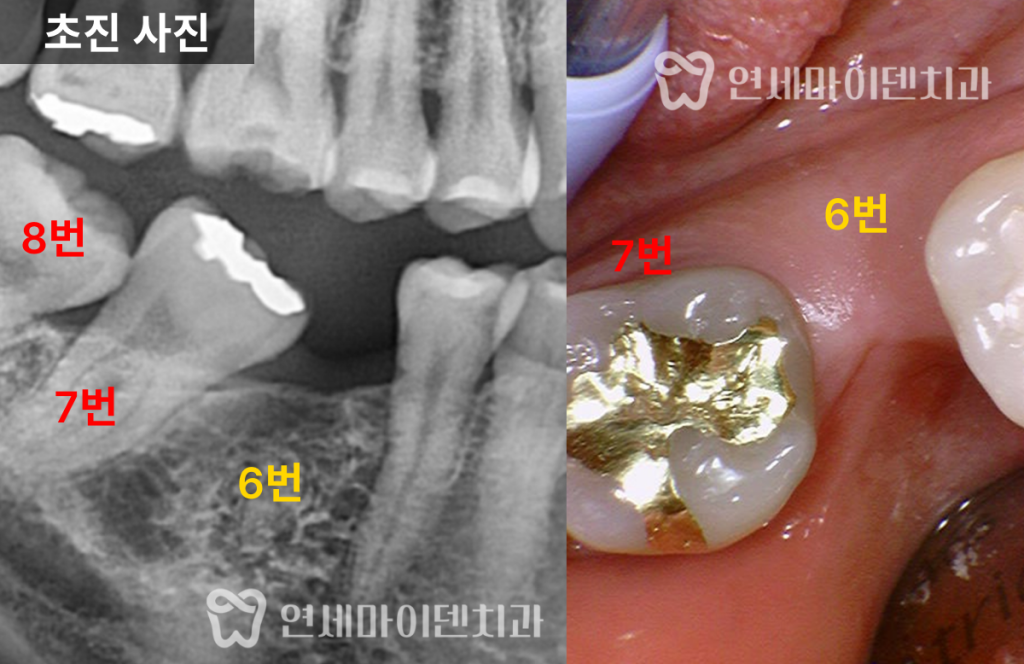

앞 치아는 자연치로 살렸습니다.발치 후 상태와 문제점

환자분은 오랫동안 통증을 참고 지내다

결국 어금니 하나를 발치한 상태로 내원하셨습니다.

X-ray를 확인해보면,

반대편 어금니는 뼈 상태가 비교적 건강한 반면문제 부위는 치조골 높이가

절반 가까이 무너진 상태였습니다이 때문에 이전 병원에서는

“앞 치아도 곧 못 쓴다”며

두 개 모두 임플란트를 권유받았던 상황이었습니다.

하지만, 앞쪽 어금니의 경우

뿌리 앞쪽 뼈는 비교적 단단하게 남아 있었고

염증 범위도 제한적이어서

충분히 보존 가능성이 있는 상태였습니다.즉,

무조건 두 개를 다 뽑아야 할 상황은 아니었습니다.치료 방향: “하나는 살리고, 하나는 심자”